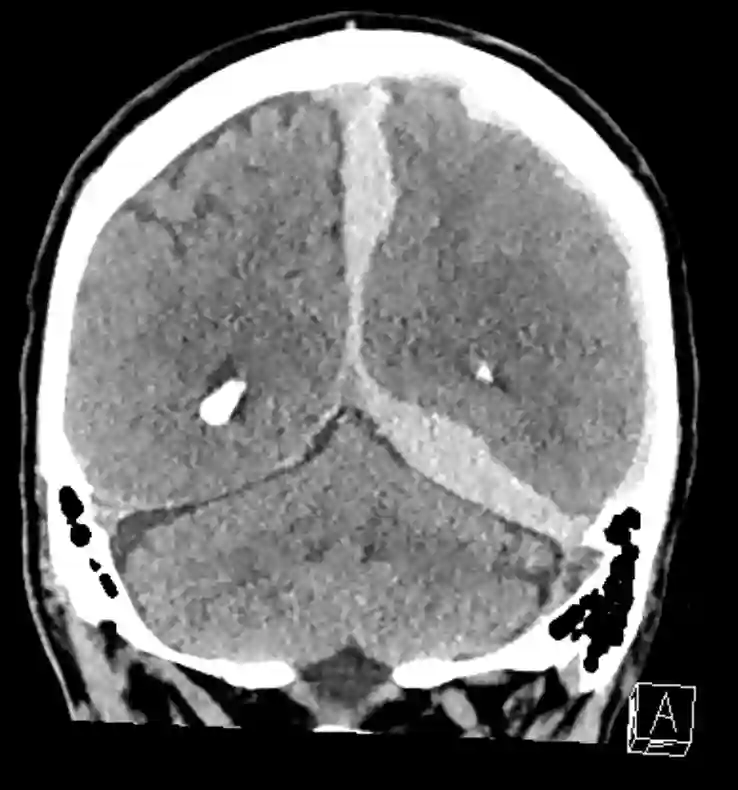

Interhemisphärisches Subduralhämatom

Coronares CT Bild eines Patienten mit einem akuten interhemisphärischen und tentoriellem akuten Subduralhämatom.